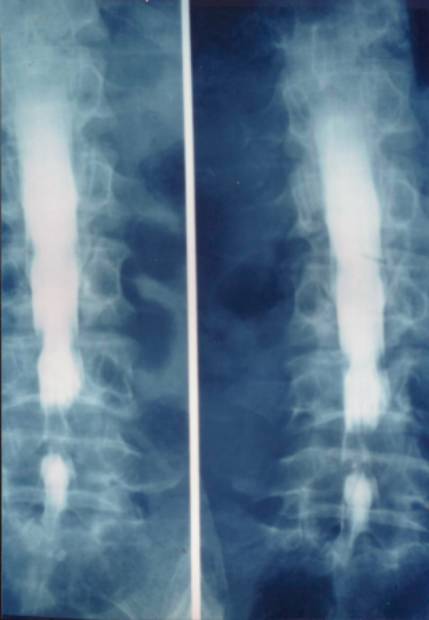

2、椎管造影:椎管造影在诊断椎管狭窄症中有重要价值。能直接在荧光透视下动态观察造影剂在椎管内流动情况。显示椎管、硬膜囊、神经根袖全貌。

但椎管造影为有创性检查,患者不易接受。侧隐窝病变不能清晰显示,不能显示椎管横断面骨和神经根形态。

腰椎管狭窄者椎管造影均有不同程度的造影剂充盈缺损。完全梗阻断处常呈幕帘状、笔尖状,弹头状样充盈缺损。不完全梗阻断处常呈点滴状通过,其结果呈葫芦状、哑铃状或灯笼状等。

前屈后伸位造影对比

椎管造影

中央型椎管狭窄突出

造影斜位可清晰显示神经根袖